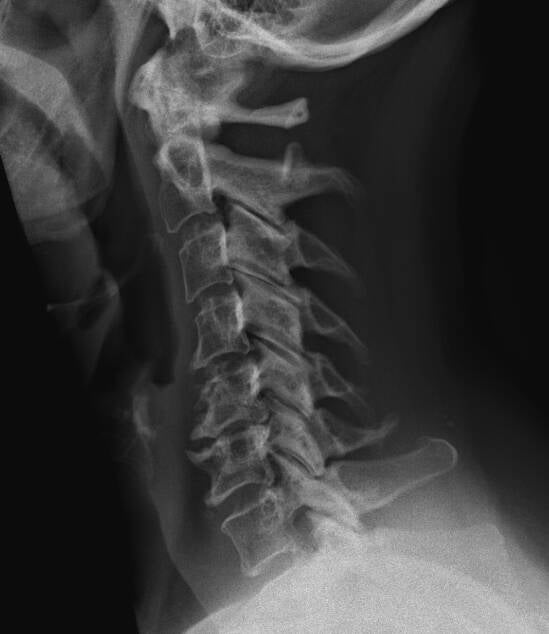

So what's got me agitated? This x-ray.

Now, that doesn't look good, does it? For five days, before the report came in today, I studied this and mulled over it, coming to the conclusion (in combination with my symptoms) that I probably need surgery. Now, I don't like to freak out about things, and I'm an excellent amateur researcher, so of course I referred to photos of normal scans, photos of scans of various types of arthritic damage, photos of implants, and so on. I read scholarly papers and patient testimonials and teaching materials for orthopedics students, and I've learned a great deal. I eagerly awaited the report, anxious to compare my conclusions with those of the radiology tech who examined them. Now that it's here, I find that it says "discopathy and arthritis". Well, I can see that! Sheesh.

It is worth mentioning in her defense that the really collapsed disc on this x-ray was nowhere near that flattened out three years ago when she drew that conclusion, so I don't blame her for that part. However, her dismissive attitude and general irritation also gave me a "why bother" complex about trying to get help when things continued to get worse; what was the point if I wasn't going to be taken seriously? It's only after a dramatic increase in my symptoms/decrease in my abilities, which I now blame on having dealt with the Brick Pile in the garden last spring and summer, that I decided that it was definitely coming from my neck after all and absolutely getting worse. Still, even though editing photos is agonizing for my shoulder and it's hard to find a position to get any sleep in, I didn't go in – there's a pandemic on, and I don't like to waste people's time when all they can do is send me to physiotherapy when I don't have enough physiotherapy appointments available in a year anyway to see properly to any one thing, I'm used to pain, I still assumed there wasn't really anything anybody could do anything about it, blah blah blah. Yeah, I'm a dumbass, I know. Only in the last couple of months, with increasing weakness and pain all through my arm and absolutely constant neck and shoulder pain, have I considered going in, but I was busy with my left hand, with its arthritic thumb, and didn't want to keep piling things onto myself. However, my ergotherapist announced recently that we couldn't keep doing strengthening exercises for my left arm until my neck was looked at and something done about it. Thus, this x-ray.